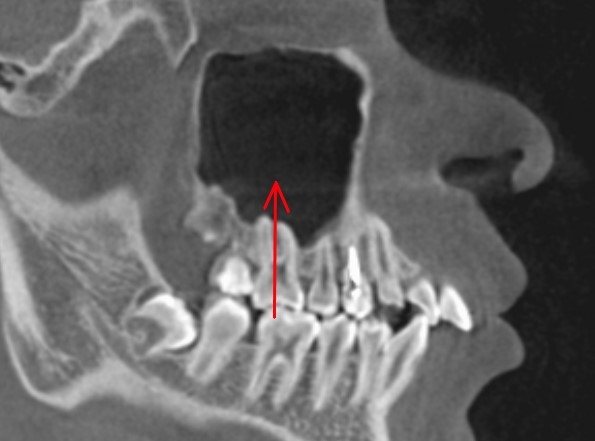

頬骨 痛いとき 急性上顎洞炎の治療 根管治療 CTで根管長測定1

根管治療の前に、CTで根管長測定します。

18.6mm。

横から見た歯です。

頬骨 痛いとき 急性上顎洞炎の治療 根管治療 CTで根管長測定2

後から見た歯です。

根管長は、18.9mです。

顔が痛い 頬骨も痛い とき 治療 根管治療

上で根管長測定した長さで、

根管を掃除します。

できれば、

歯の内部から、上顎洞まで、

開通させます。

顔が痛い 頬骨も痛い とき 根管治療 排膿

上顎洞内の膿は、

歯の内部から、膿を吸い出すこともできます。

この様に、根管治療し、

顔や頬骨が痛い事もなくなりました。

今回の急性上顎洞炎の原因は、

大きな虫歯治療の後、

神経が死んで、根管が化膿したためでした。